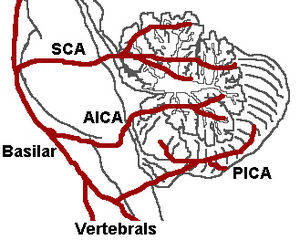

Blood supply

Three arteries supply blood to the cerebellum (Fig. 7): the superior cerebellar artery (SCA), anterior inferior cerebellar artery (AICA), and posterior inferior cerebellar artery (PICA).

Superior cerebellar artery

The SCA branches off the lateral portion of the basilar artery, just inferior to its bifurcation into the posterior cerebral artery. Here it wraps posteriorly around the pons (to which it also supplies blood) before reaching the cerebellum. The SCA supplies blood to most of the cerebellar cortex, the cerebellar nuclei, and the middle and superior cerebellar peduncles.

Anterior inferior cerebellar artery

The AICA branches off the lateral portion of the basilar artery, just superior to the junction of the vertebral arteries. From its origin, it branches along the inferior portion of the pons at the cerebellopontine angle before reaching the cerebellum. This artery supplies blood to the anterior portion of the inferior cerebellum, and to the facial (CN VII) and vestibulocochlear nerves (CN VIII).

Obstruction of the AICA can cause paresis, paralysis, and loss of sensation in the face; it can also cause hearing impairment. Moreover, it could cause an infarct of the cerebellopontine angle. This could lead to hyperacusia (dysfunction of the stapedius muscle, innervated by CN VII) and vertigo (wrong interpretation from the vestibular semi-circular canal's endolymph acceleration caused by alteration of CN VIII).

Posterior inferior cerebellar artery

The PICA branches off the lateral portion of the vertebral arteries just inferior to their junction with the basilar artery. Before reaching the inferior surface of the cerebellum, the PICA sends branches into the medulla, supplying blood to several cranial nerve nuclei. In the cerebellum, the PICA supplies blood to the posterior inferior portion of the cerebellum, the inferior cerebellar peduncle, the nucleus ambiguus, the vagus motor nucleus, the spinal trigeminal nucleus, the solitary nucleus, and the vestibulocochlear nuclei.